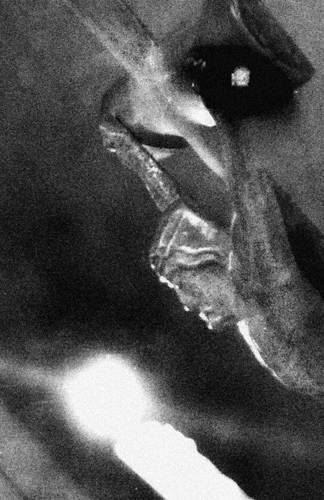

Keringat dingin dan degup jantungku semakin berpacu, begitu kereta ku berhenti di bawah lampu operasi yang besar dan ruangan yang penuh dengan peralatan, selang dan kabel-kabel. Aku pasrah ketika kedua tanganku di ikat dan badanku mulai dipasang kabel-kabel monitor jantung. Akhirnya aku tergeletak tak berdaya setelah jarum anestesi menusuk punggungku. Terasa ribuan semut merayapi bagian pinggang ke bawah hingga ke ujung-ujung jari kaki. Tak berapa lama pinggang ke bawah sudah tidak terasa seakan aku tidak memiliki kaki lagi. Operasi pun dimulai, aku memberanikan diri melihat prosesnya dari monitor yang bisa aku lihat. Alat-alat dari besi berbentuk semacam ujung cacing mulai merayapi badan dalamku, mencari jalur masuk menuju batu yang menyumbat. Semakin tegang detik-demi detik bergulir dengan lambat, hingga akhirnya suara dokter jelas memcahkan kebisuan “itu batunya mas”. Lega akhirnya batu yang menyumbat saluran ginjalku ditemukan. Proses selanjutnya aku mengamati dari monitor bagaimana batu itu mulai dihancurkan. “ Det, det det…. Det det det “ bunyi mesin yang keras terdengar setiap kali proses penembakan batu dilakukan. Sekitar 10 menit saluran ginjalku sudah bersih dari batu yang dimonitor berwarna kuning.